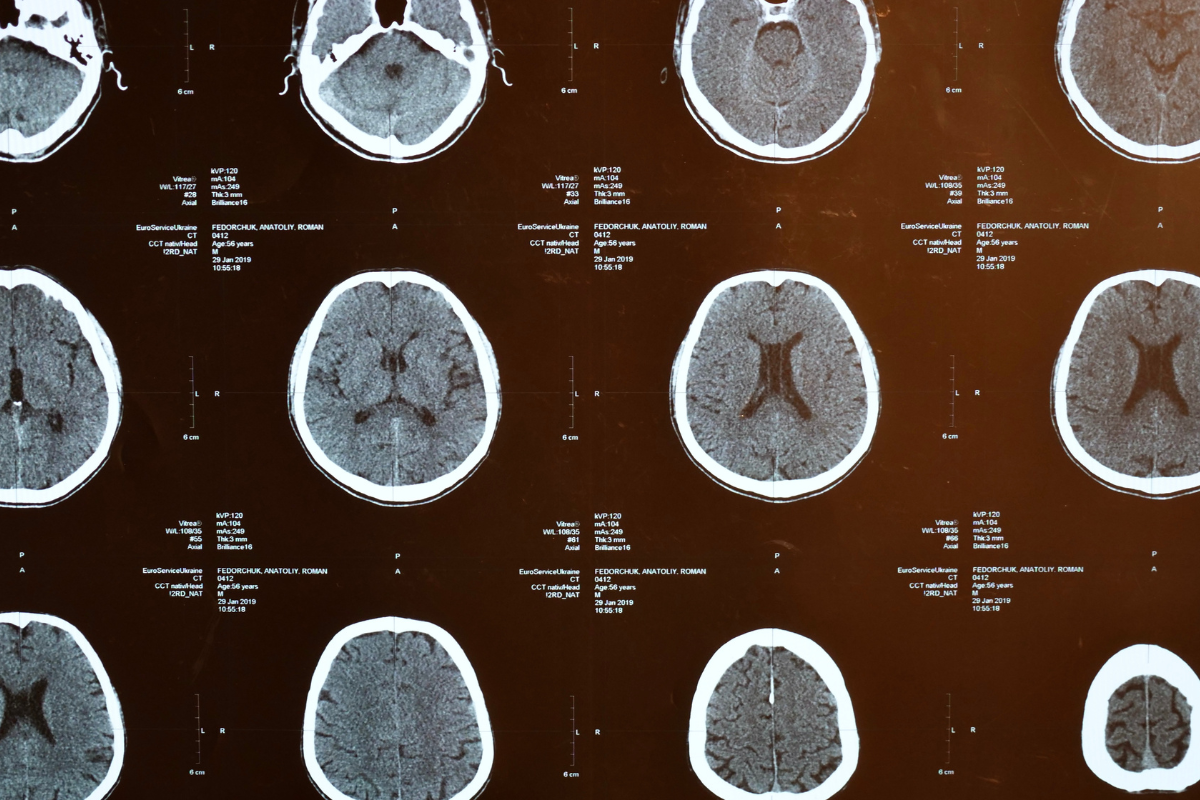

A groundbreaking study published in Nature Medicine in April 2025 has identified a new type of brain lesion—the broad rim lesion (BRL)—which may predict rapid disease progression in multiple sclerosis (MS). While researchers suggest BRLs could serve as biomarkers for aggressive MS, the findings inadvertently support a perspective that we have long advocated: MS is